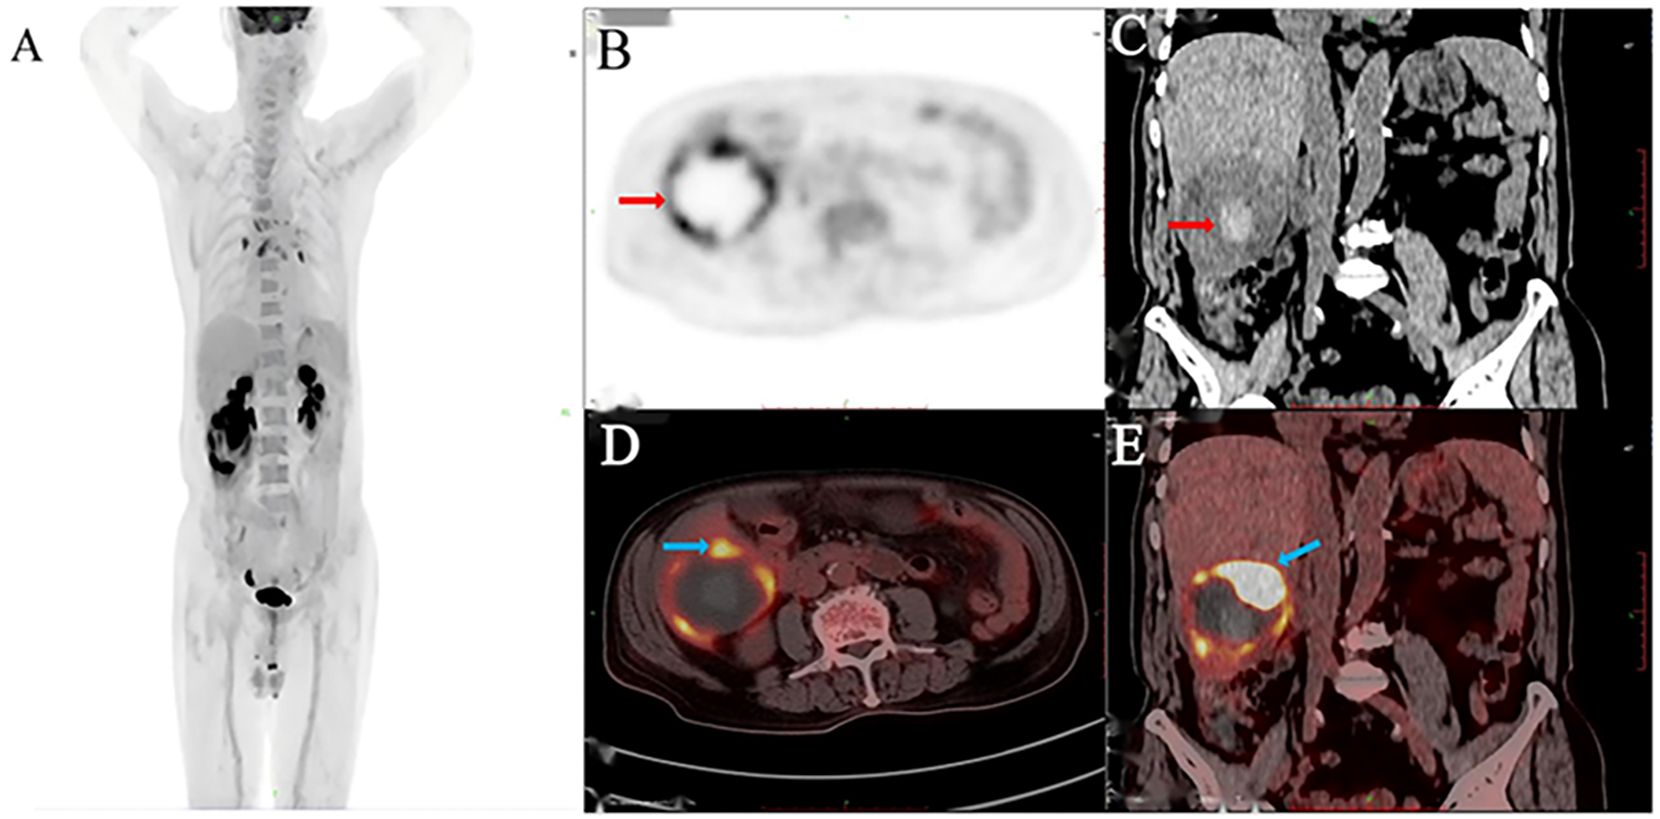

Pembrolizumab combined with surgical treatment for spontaneously ruptured undifferentiated pleomorphic sarcoma of the liver: A case report and literature review

Undifferentiated pleomorphic sarcoma of the liver (UPSL) is a rare pathological type characterized by an undefined mechanism, low incidence, high metastatic rate, aggressive behavior, and an inferior prognosis; no standardized treatment protocols or guidelines currently exist. This article reports the case of an 83-year-old male with UPSL confirmed through surgical resection and pathological biopsy. Postoperatively, he received eight cycles of pembrolizumab, which resulted in a favourable clinical efficacy. With advances in medical technology, the integration of surgery and immunotherapy is expected to play an essential role in treating this rare disease and monitoring its prognosis.